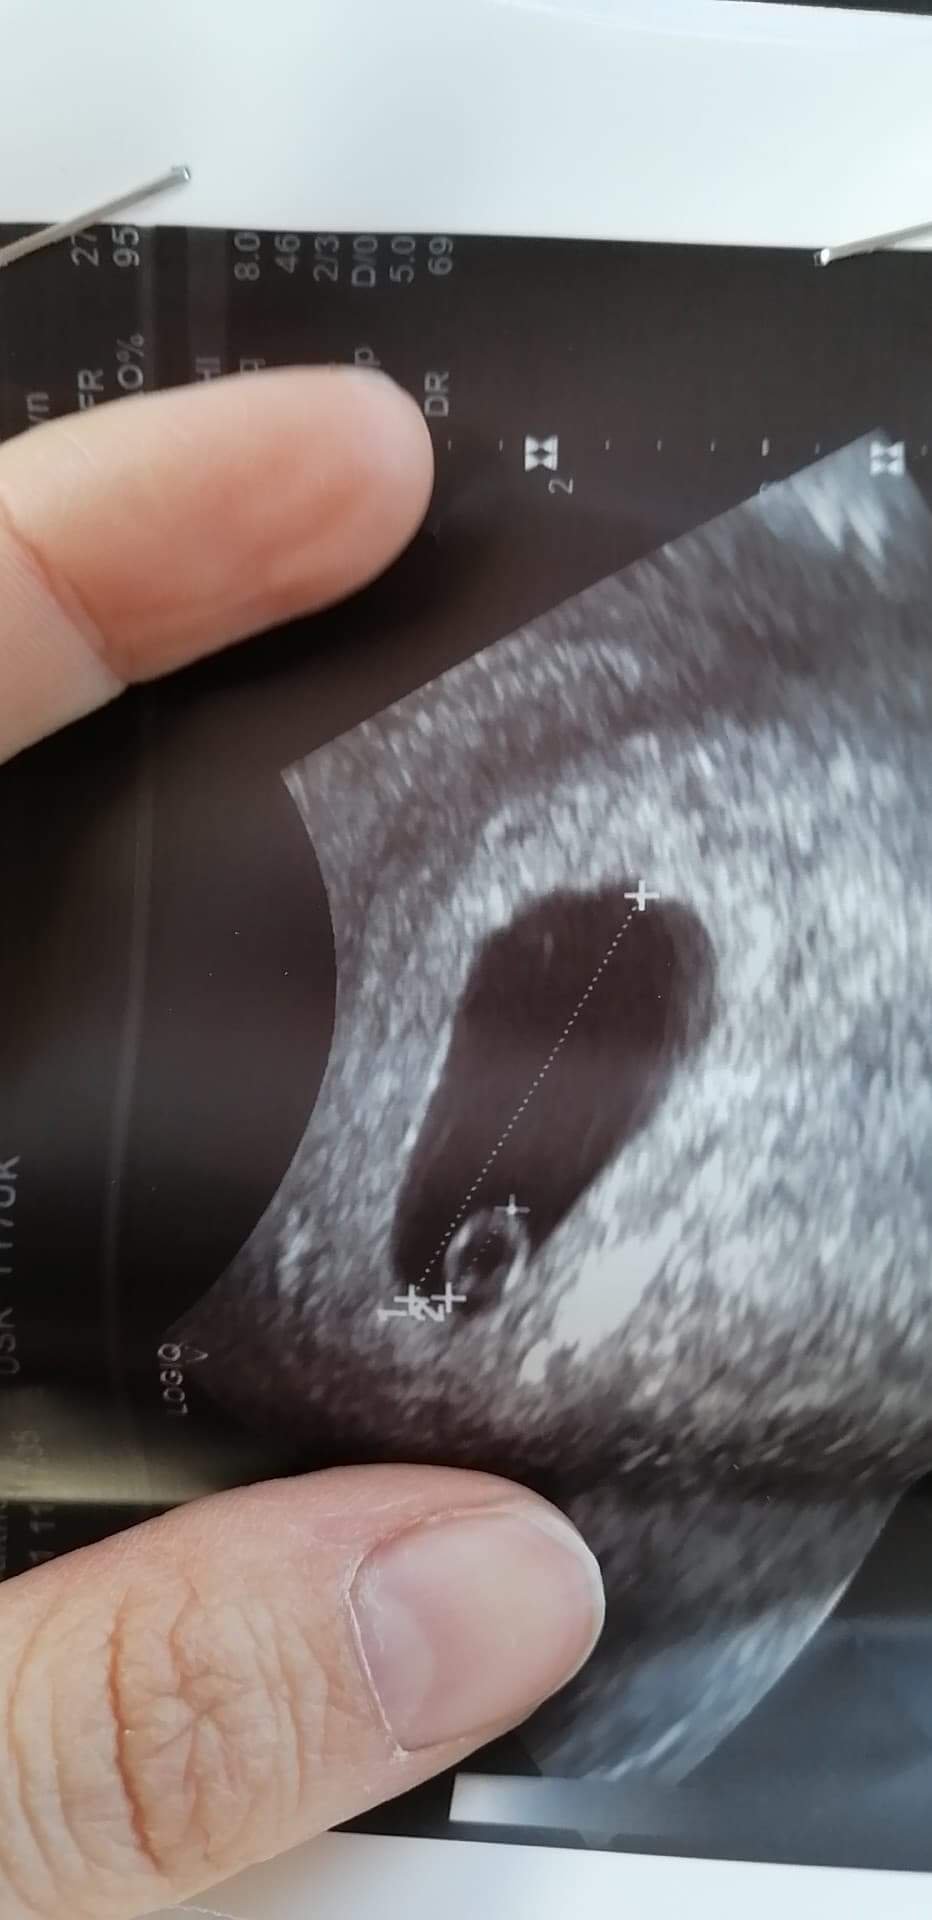

To takie kółeczko. Ale widzę ze lekarz napisał YS i wymiary a to właśnie pęcherzyk zoltkowy! A od tego czasu dzień dwa dni później powinien być już zarodeczekTo jest to czarne w środku?

YS to pęcherzyk żółtkowy (yolk sac YS)Dziękuję wam za pocieszenie :* odpisuję zbiorczo. Byłam w piątek i było 7mm i dziś trochę więcej więc coś tam się rozwija. Zarówno w piątek jak i dziś widać było tylko pęcherzyk ciążowy. Załączam opisy z obu usg i zdjęcie z dziś. Zobacz załącznik 1277420Zobacz załącznik 1277421Zobacz załącznik 1277422

Tak słyszałam o tej teorii, jestem ciekawa na ile się sprawdzi [emoji6]Dziękuję wam za pocieszenie :* odpisuję zbiorczo. Byłam w piątek i było 7mm i dziś trochę więcej więc coś tam się rozwija. Zarówno w piątek jak i dziś widać było tylko pęcherzyk ciążowy. Załączam opisy z obu usg i zdjęcie z dziś. Zobacz załącznik 1277420Zobacz załącznik 1277421Zobacz załącznik 1277422